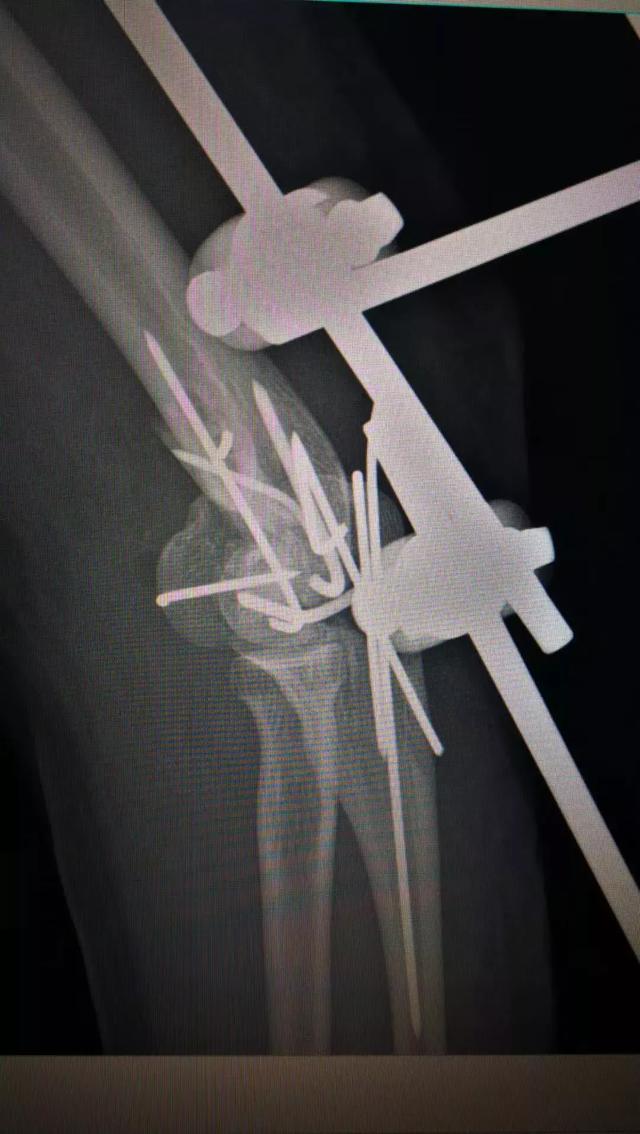

于是,张主任带领团队凌晨急诊给她做了肘部扩创、血管神经肌腱关节囊探查修复、局部皮瓣转移、肱骨骨折尺骨骨折切开复位内固定+骨折外固定关节外固定架固定、食指近节指骨骨折內固定术。此类手术需要医生极为细致与耐心,还要在术中不断地评估决策,为伤员的短期与长期利益决定出最佳方案。

.术前术后对比图